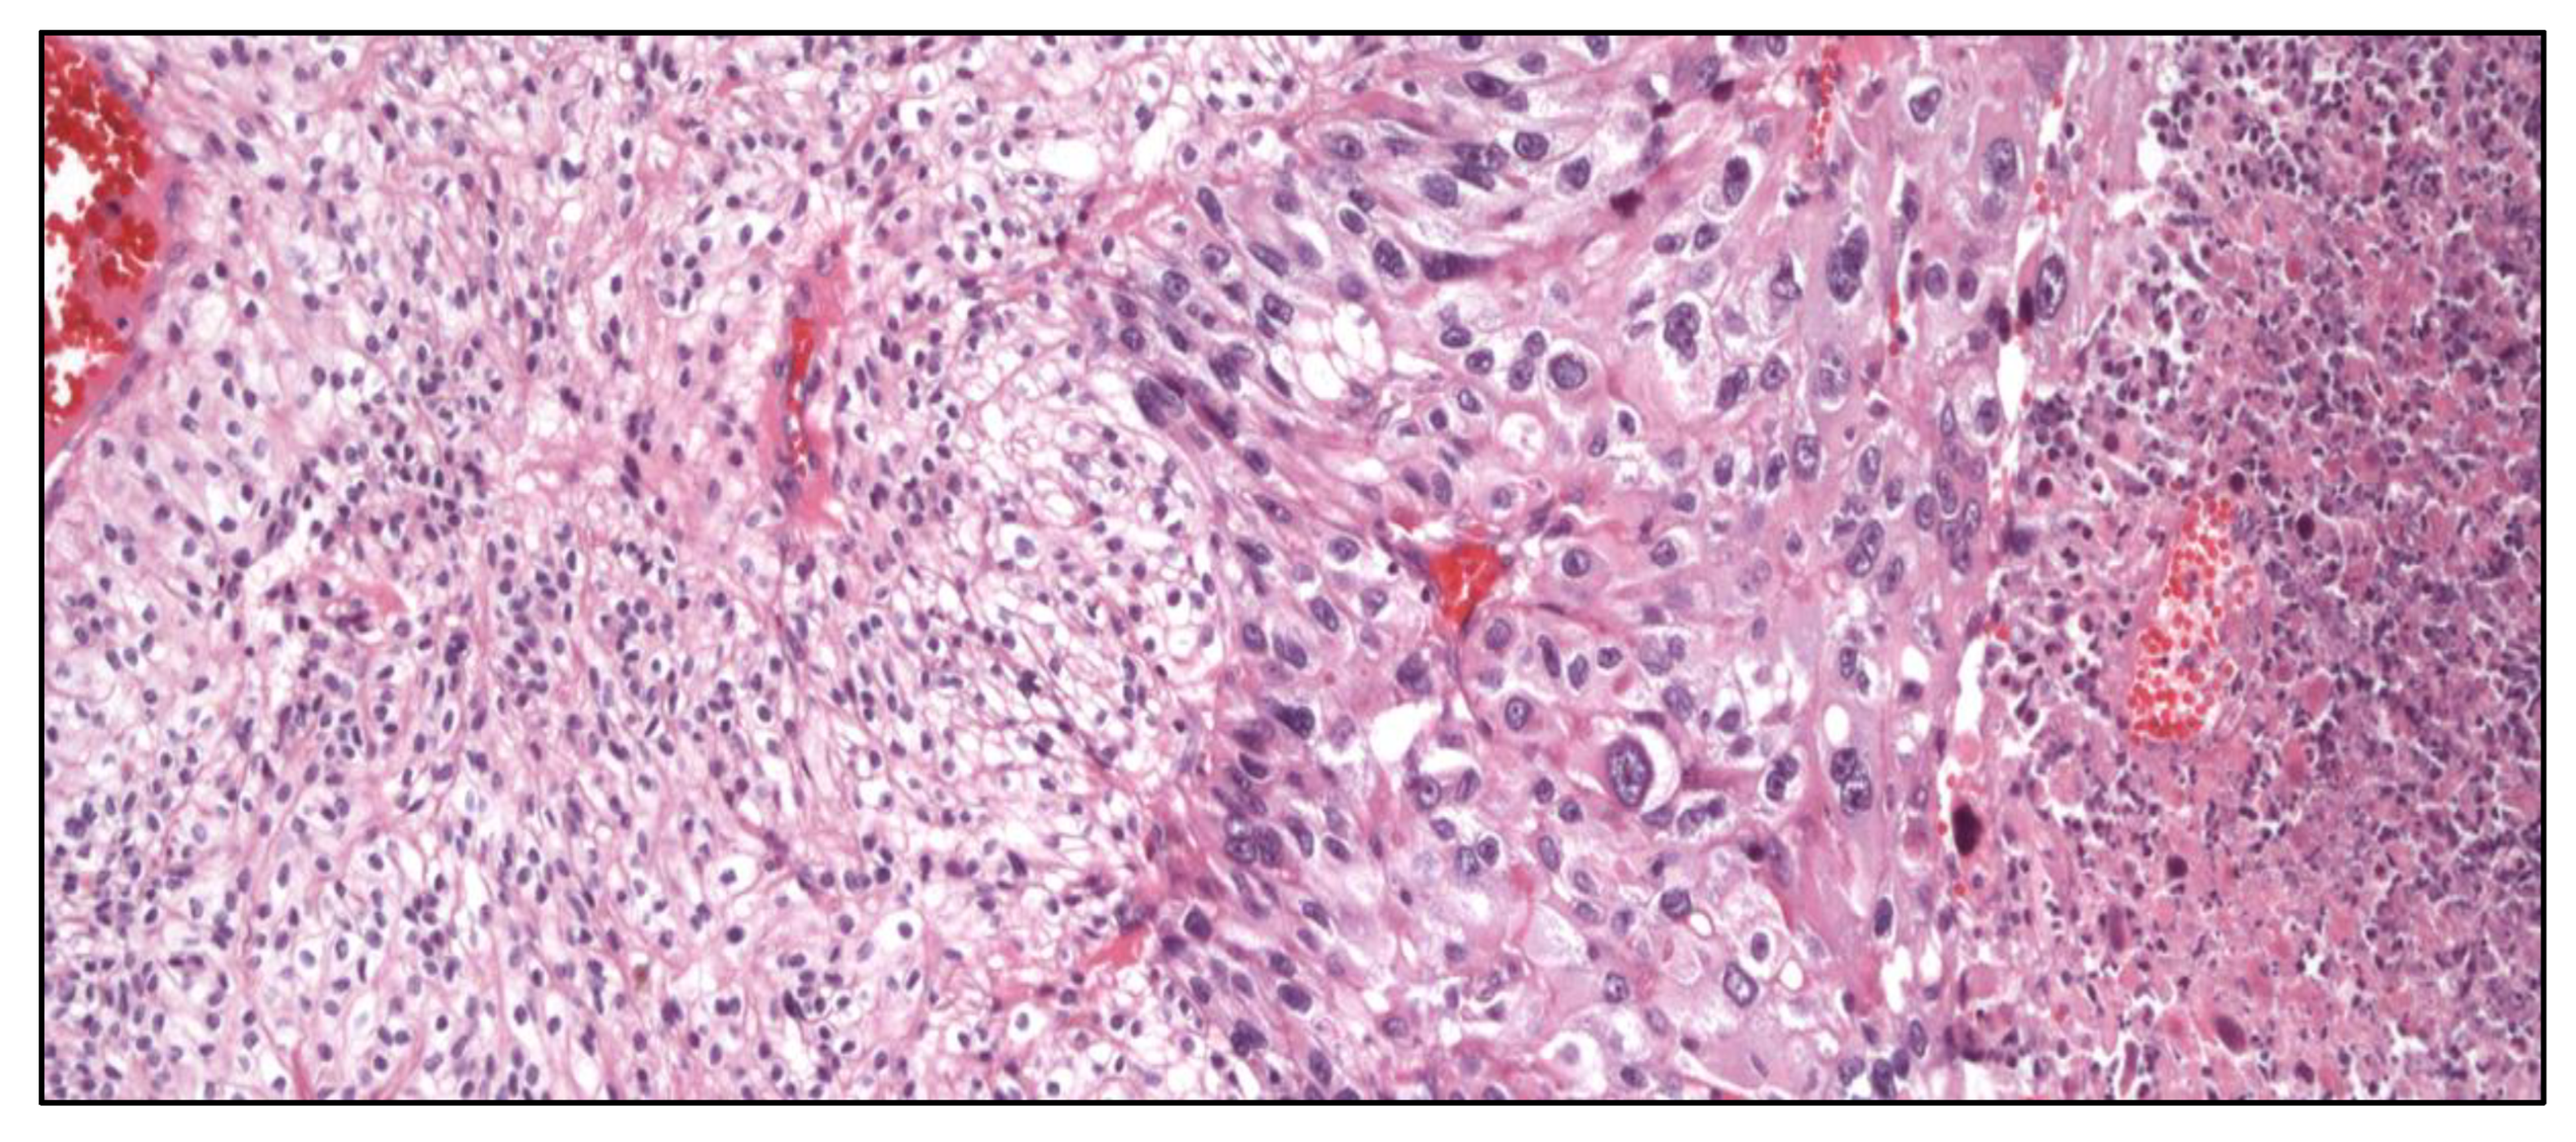

The presence of a cribriform pattern worsens the prognosis of Gleason indexes 3+4, 4+3, and 4+4. Also, large (>12 lumina) cribriform structures (Figure 1) impact negatively the prognosis of PCa.

Figure 1. Big cribriform structures indicative or poorer prognosis in a prostate adenocarcinoma.